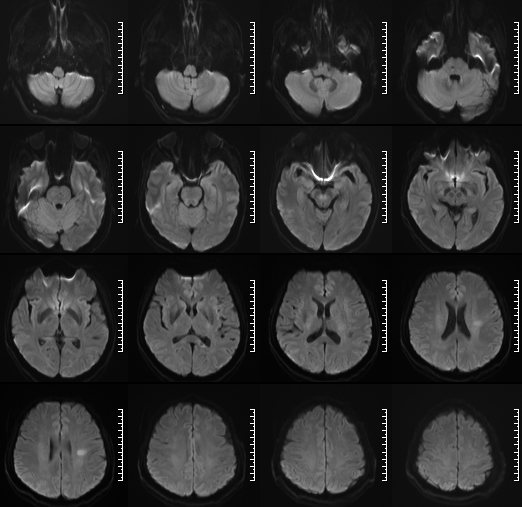

畅医达(Accessway)0.017支架微导管在0.014微导丝引导下顺利到达右侧大脑中动脉M2远端,经支架微导管引入畅医达(Choydar)血流导向装置,3mm*15mm,推送平顺,然后跨瘤颈缓慢释放支架,支架头端打开良好。

支架部分释放后复查造影示支架位置良好,缓慢完全释放支架,支架打开良好,复查造影示支架位置良好,完全覆盖瘤颈,贴壁佳,瘤囊内可见造影剂滞留明显,OKM分级A3。

Vaso CT显示 畅医达(Choydar)血流导向装置 位置良好,完全覆盖瘤颈,长轴及横轴薄层均显示支架贴壁良好。

术后即刻正侧位造影显示载瘤动脉及远端分支显影无异常,瘤囊内可见明显造影剂滞留;Xper-CT未见出血。